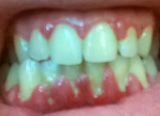

κλινική εικόνα ουλίτιδας περιοδοντίτιδα σε γυναίκα 22 ετών ακτινογραφική εικόνα περιοδοντίτιδας